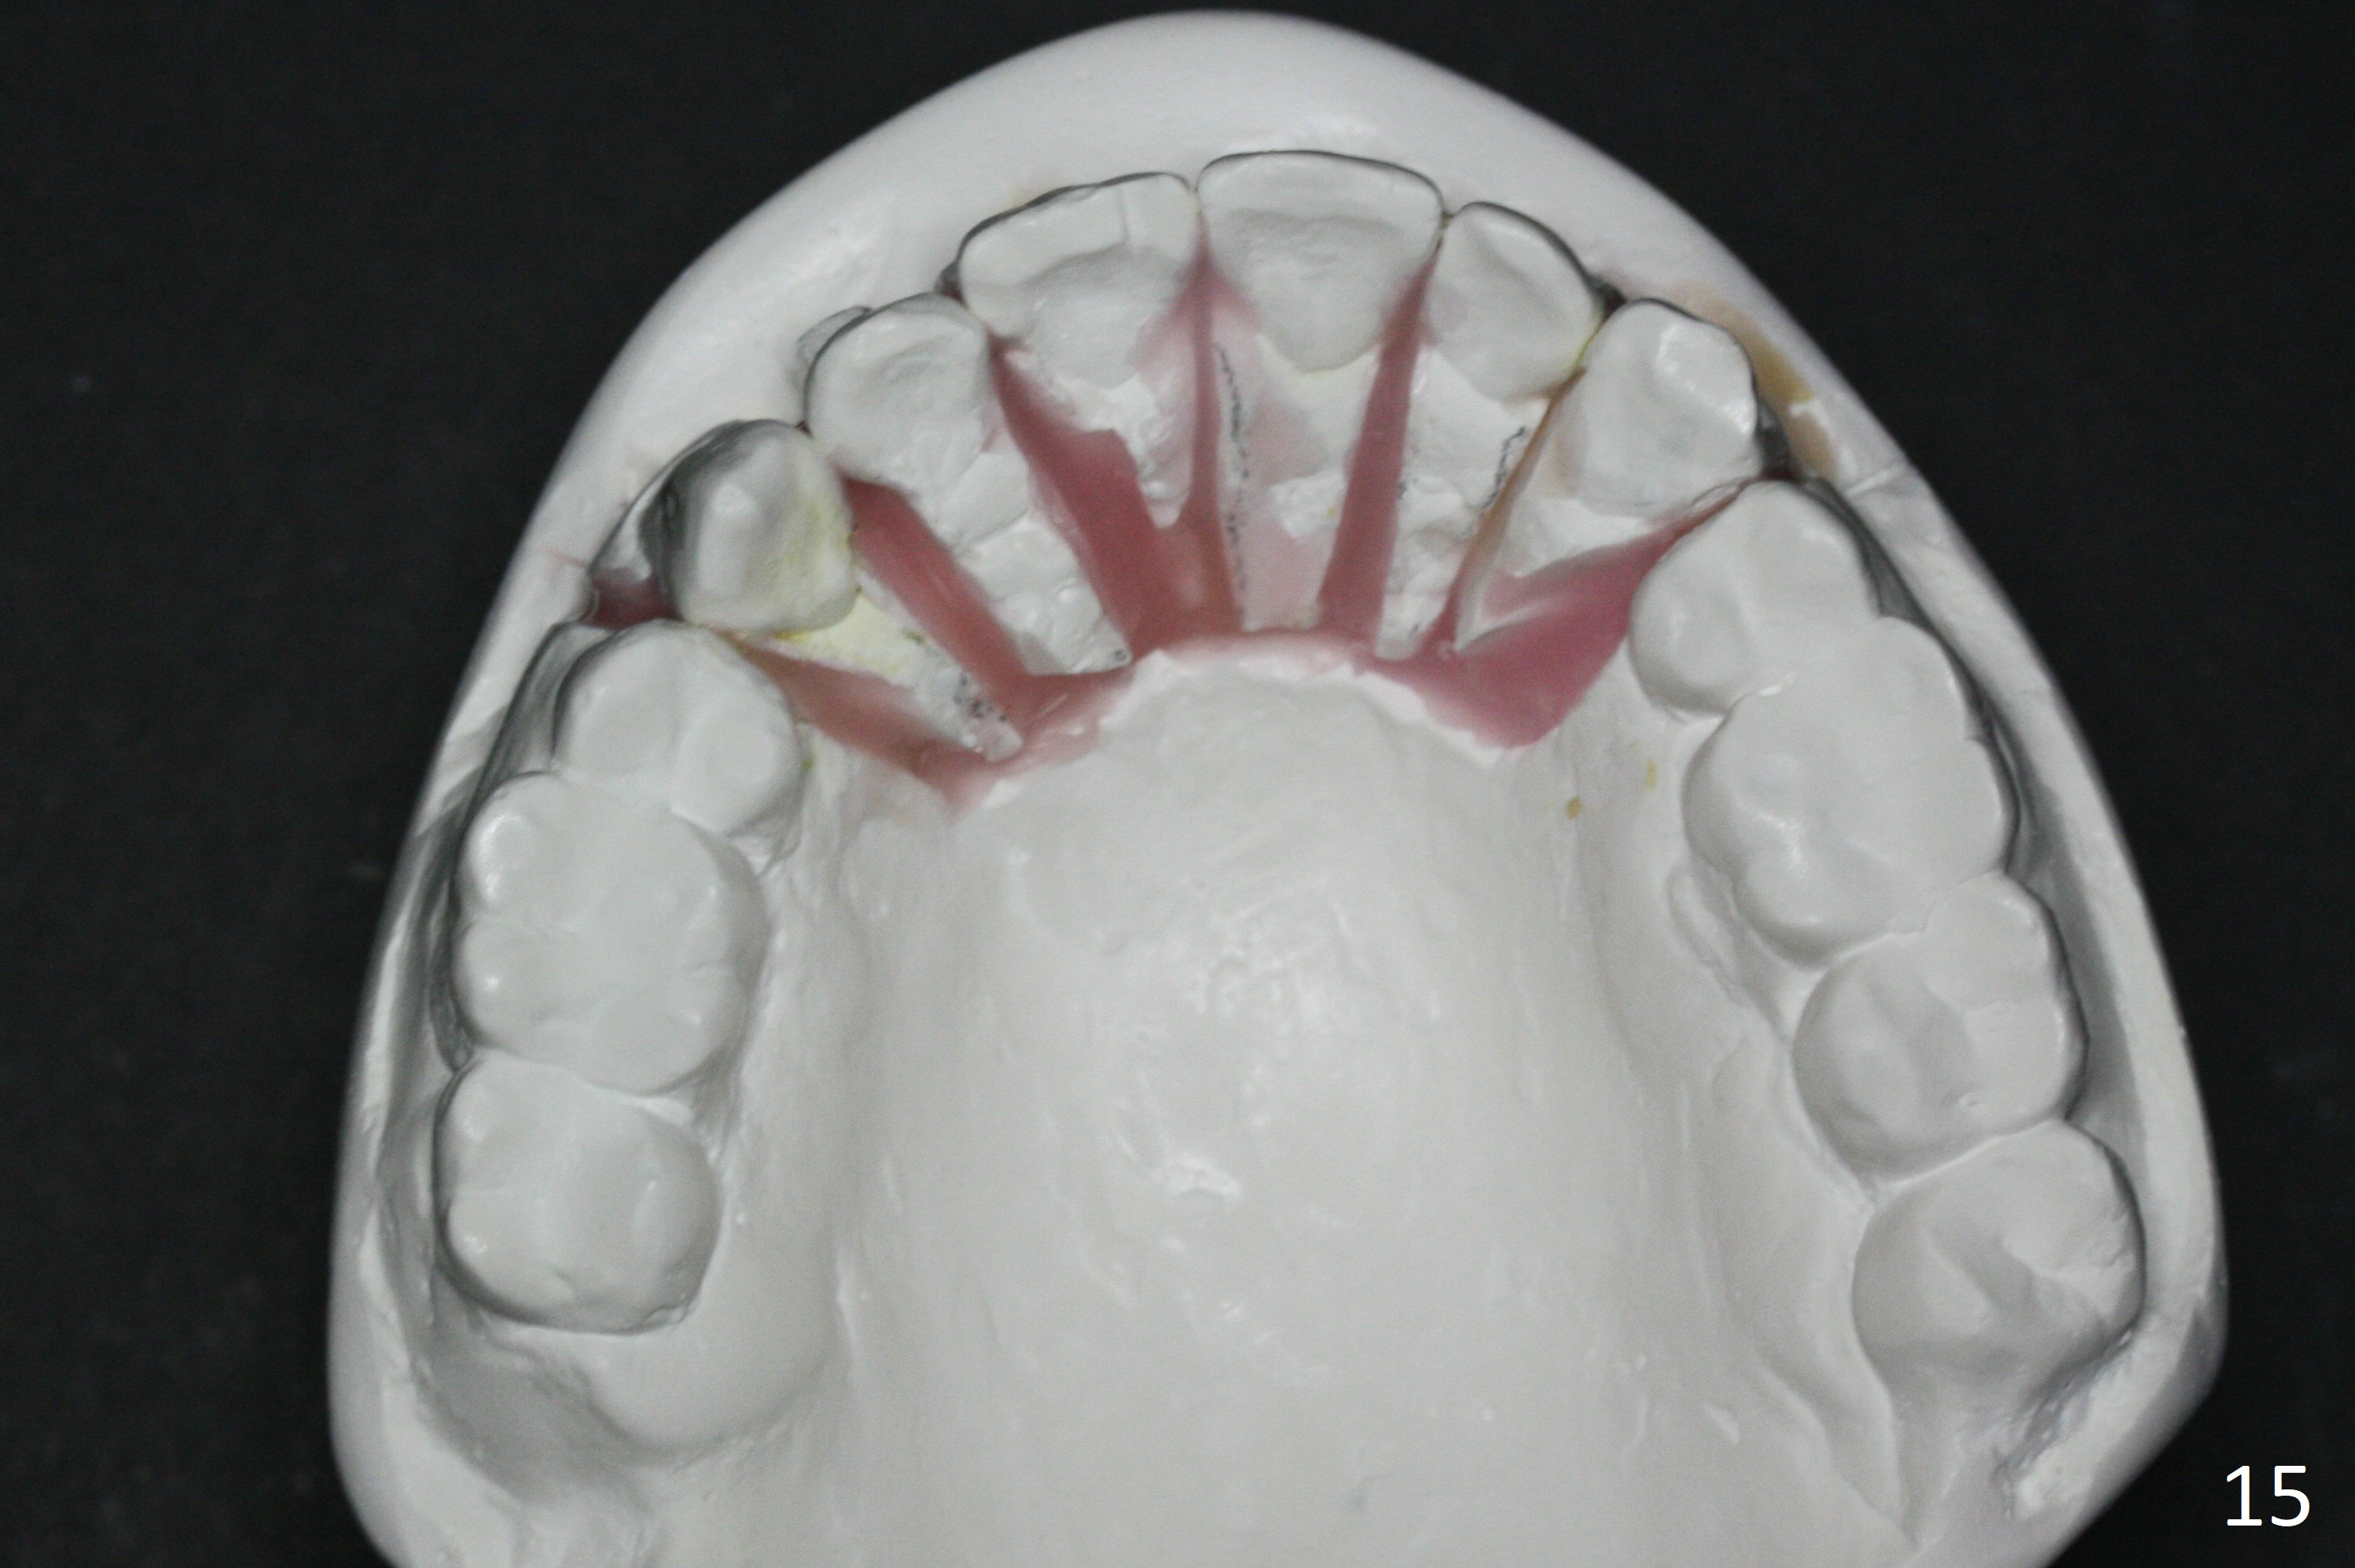

Enough Space For Crowding After Extraction? A 47-year-old man requests orthodontic treatment following SRP in other office (Fig.1-11). For severe crowding and midline shifting, extraction of four of the 1st bicuspids is imminent. Is it enough? To answer the question, model surgery is performed (Fig.12-16). 1st visit: periodontal maintenance, orthodontic consent (emphasizing oral hygiene) extract 4s and possibly L8s and separators. The beauty of this vist is that after local anesthesia and extraction including L8s, it is painless and easy to remove calculus from the proximal surfaces of the neighboring teeth. It is much easier to place separators after extraction. It is expected that there is no gingival erythema when the patient returns for bracketing. Take photos of UR3, similar to Fig.3. Molar banding is also anticipated to be easy with separator placement after extraction. Return to Ortho Cases Xin Wei, DDS, PhD, MS 1st edition 11/23/2017, last revision 04/28/2019